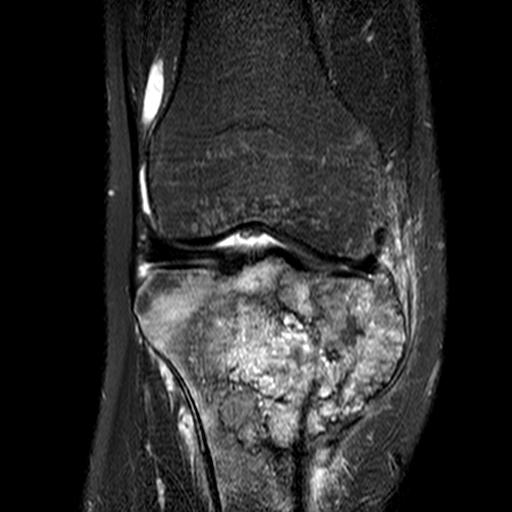

MRI

Evaluate

i) Soft tissue component

ii) Involvement of neurovascular bundle

iii) Marrow extent of tumour

- helpful in determining appropriate resection level

- satellite lesions - metastasis within reactive zone

iv) Identify skip lesions

- metastasis outside reactive zone

- sagittal and coronal images of the entire bone

v) Joint involvement